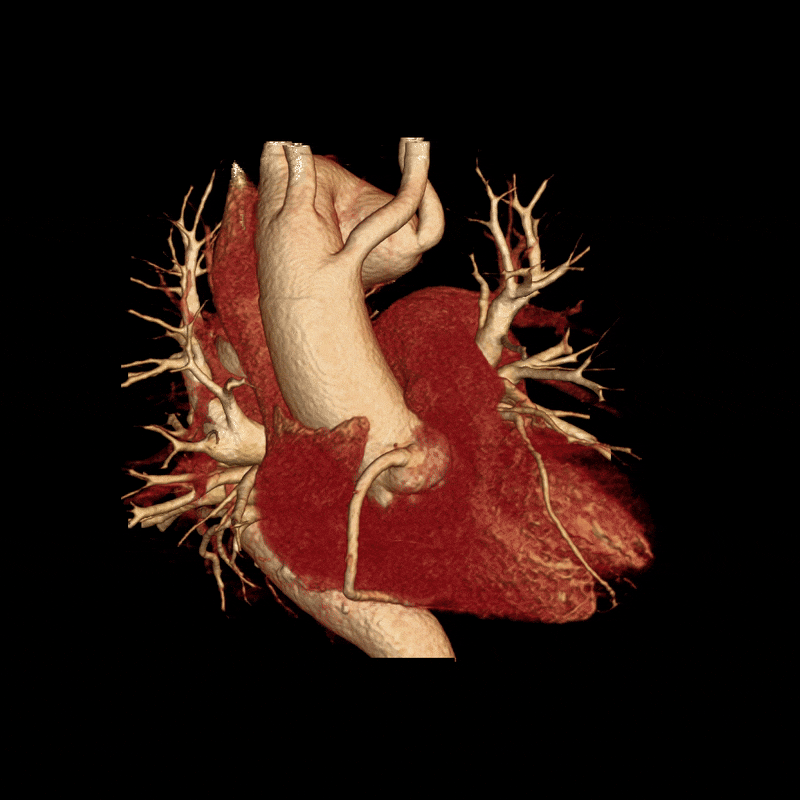

This case, however, involved unusual anatomy. The patient had a right-sided aortic arch, a congenital anomaly in which the aorta curves to the right side of the chest instead of the left. The branching pattern was also atypical. The first branch from this patient’s arch was the left common carotid artery, followed by the right common carotid and right subclavian arteries. The final branch was an aberrant left subclavian artery, which arose from a large Kommerell diverticulum, an outpouching often associated with arch anomalies. The descending thoracic aorta was tortuous, with an aneurysm identified at its proximal portion.

A 3DQ Lab technologist processed the scan using our aortic surveillance protocol. Standardized measurements were taken at set locations along the aorta to ensure consistency with prior studies. Volume-rendered images were generated to visualize the morphology of the aorta and its branch vessels in three dimensions. Curved planar reformats of the coronary arteries were also created to assess their course and relationship to the aortic anatomy. All measurements were then added to the patient’s graph alongside those from previous visits, demonstrating how the size of the aorta has changed over time. Below are the images provided to the Cardiothoracic Surgery team.

Figure G: Targeted volume renderings of the heart, thoracic aorta, and coronary arteries for visualization of anatomy and vessel morphology. (Learn more about volume renders here).